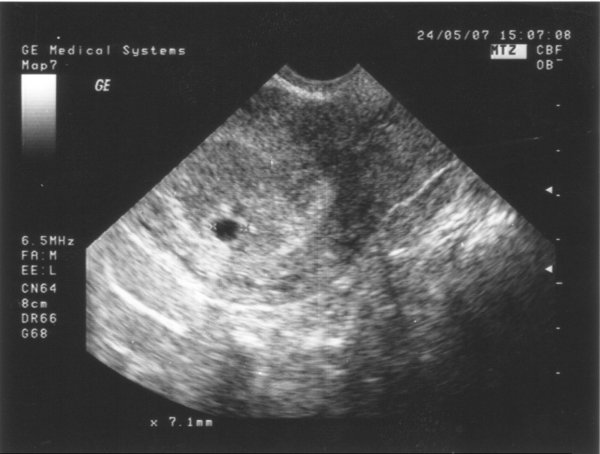

Mi volt az uh-n?